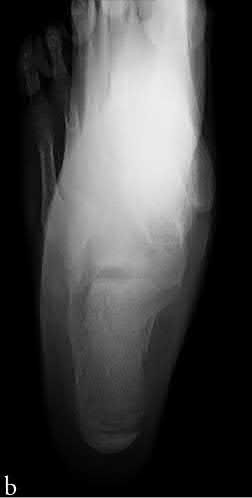

A 15-year-old male presents with knee pain, and biopsy confirms conventional high-grade osteosarcoma of the distal femur.

Following neoadjuvant chemotherapy and wide resection, what histologic finding represents the most significant prognostic factor for long-term survival in localized disease?

Explanation

In localized high-grade osteosarcoma, the degree of tumor necrosis after induction (neoadjuvant) chemotherapy is one of the most powerful prognostic indicators. A "good response" is typically defined as ≥ 90% necrosis (Huvos grade III or IV). A necrosis rate of less than 90% is an adverse prognostic factor for survival.